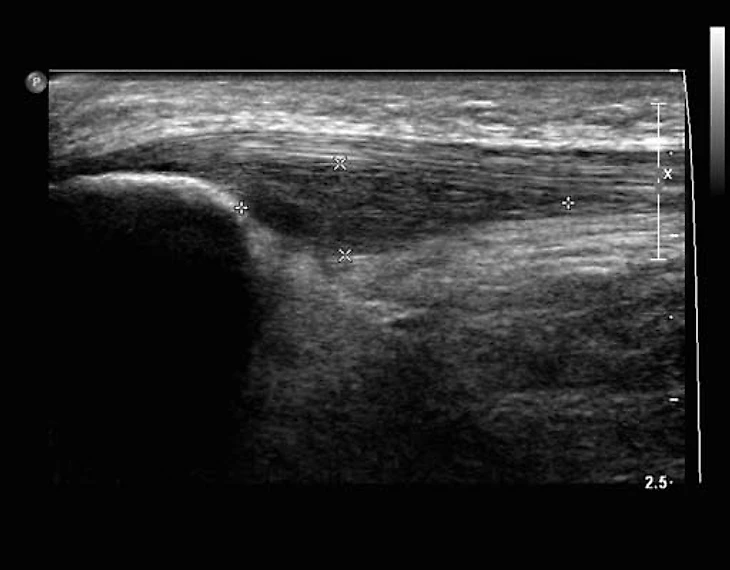

Вот, как это примерно выглядело в случае Маслова.

Как мы видим, УЗИ позволяет точнее оценить степень изменений в сухожилии, особенно это касается неоваскуляризации. Плюс, это динамический метод, то есть мы можем попросить пациента двигать ногой, сокращать мышцы бедра и оценить, как на это реагирует сухожилие. В случае МРТ мы можем оценить лишь статичную картинку. Но и у МРТ есть свои плюсы — больший объем оцениваемых тканей; позволяет оценить еще и состояние сустава, куда ультразвуковой сигнал уже не добирается. Плюс, УЗИ хороший метод только при оценке поверхностно лежащих тканей. В случае тендинопатии в других областях МРТ может оказаться точнее и более предпочтительным методом.